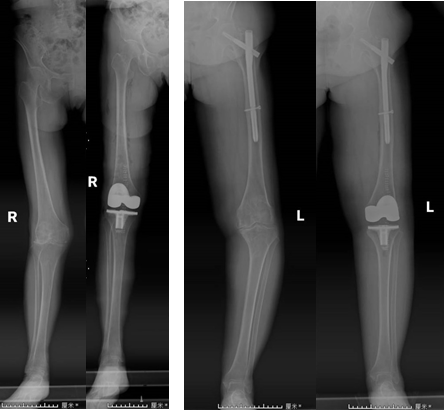

手術(shù)前后患者X線片對比

膝關(guān)節(jié)疼痛是困擾老年人常見的問題,而膝關(guān)節(jié)置換手術(shù)是治療終末期膝關(guān)節(jié)退變的主要有效手段。近日,我院關(guān)節(jié)運動醫(yī)學(xué)科康立新主任醫(yī)師團(tuán)隊,利用全膝關(guān)節(jié)手術(shù)定位系統(tǒng)(iKAPS)完成兩例復(fù)雜膝關(guān)節(jié)置換手術(shù)。該技術(shù)為膝關(guān)節(jié)畸形嚴(yán)重、股骨髓腔閉鎖或者既往股骨近端手術(shù)有內(nèi)植物的患者進(jìn)行膝關(guān)節(jié)置換,提供了一種更加精準(zhǔn)、有效的治療方法。

術(shù)中使用類似麻將牌大小的下肢力線測量儀,配合醫(yī)療交互軟件和配套工具,精準(zhǔn)地測量出股骨遠(yuǎn)端和脛骨平臺的截骨角度,輔助手術(shù)者進(jìn)行個體化的精準(zhǔn)截骨,恢復(fù)下肢力線。術(shù)中不需要打開股骨髓腔,比傳統(tǒng)手術(shù)出血少、恢復(fù)快。

全膝關(guān)節(jié)手術(shù)定位系統(tǒng)(iKPAS)可用于初次或復(fù)雜全膝關(guān)節(jié)置換手術(shù),在不開髓的情況下實現(xiàn)膝關(guān)節(jié)力線的定位,尤其針對股骨骨折內(nèi)固定物未取出的情況,優(yōu)勢更加明顯。